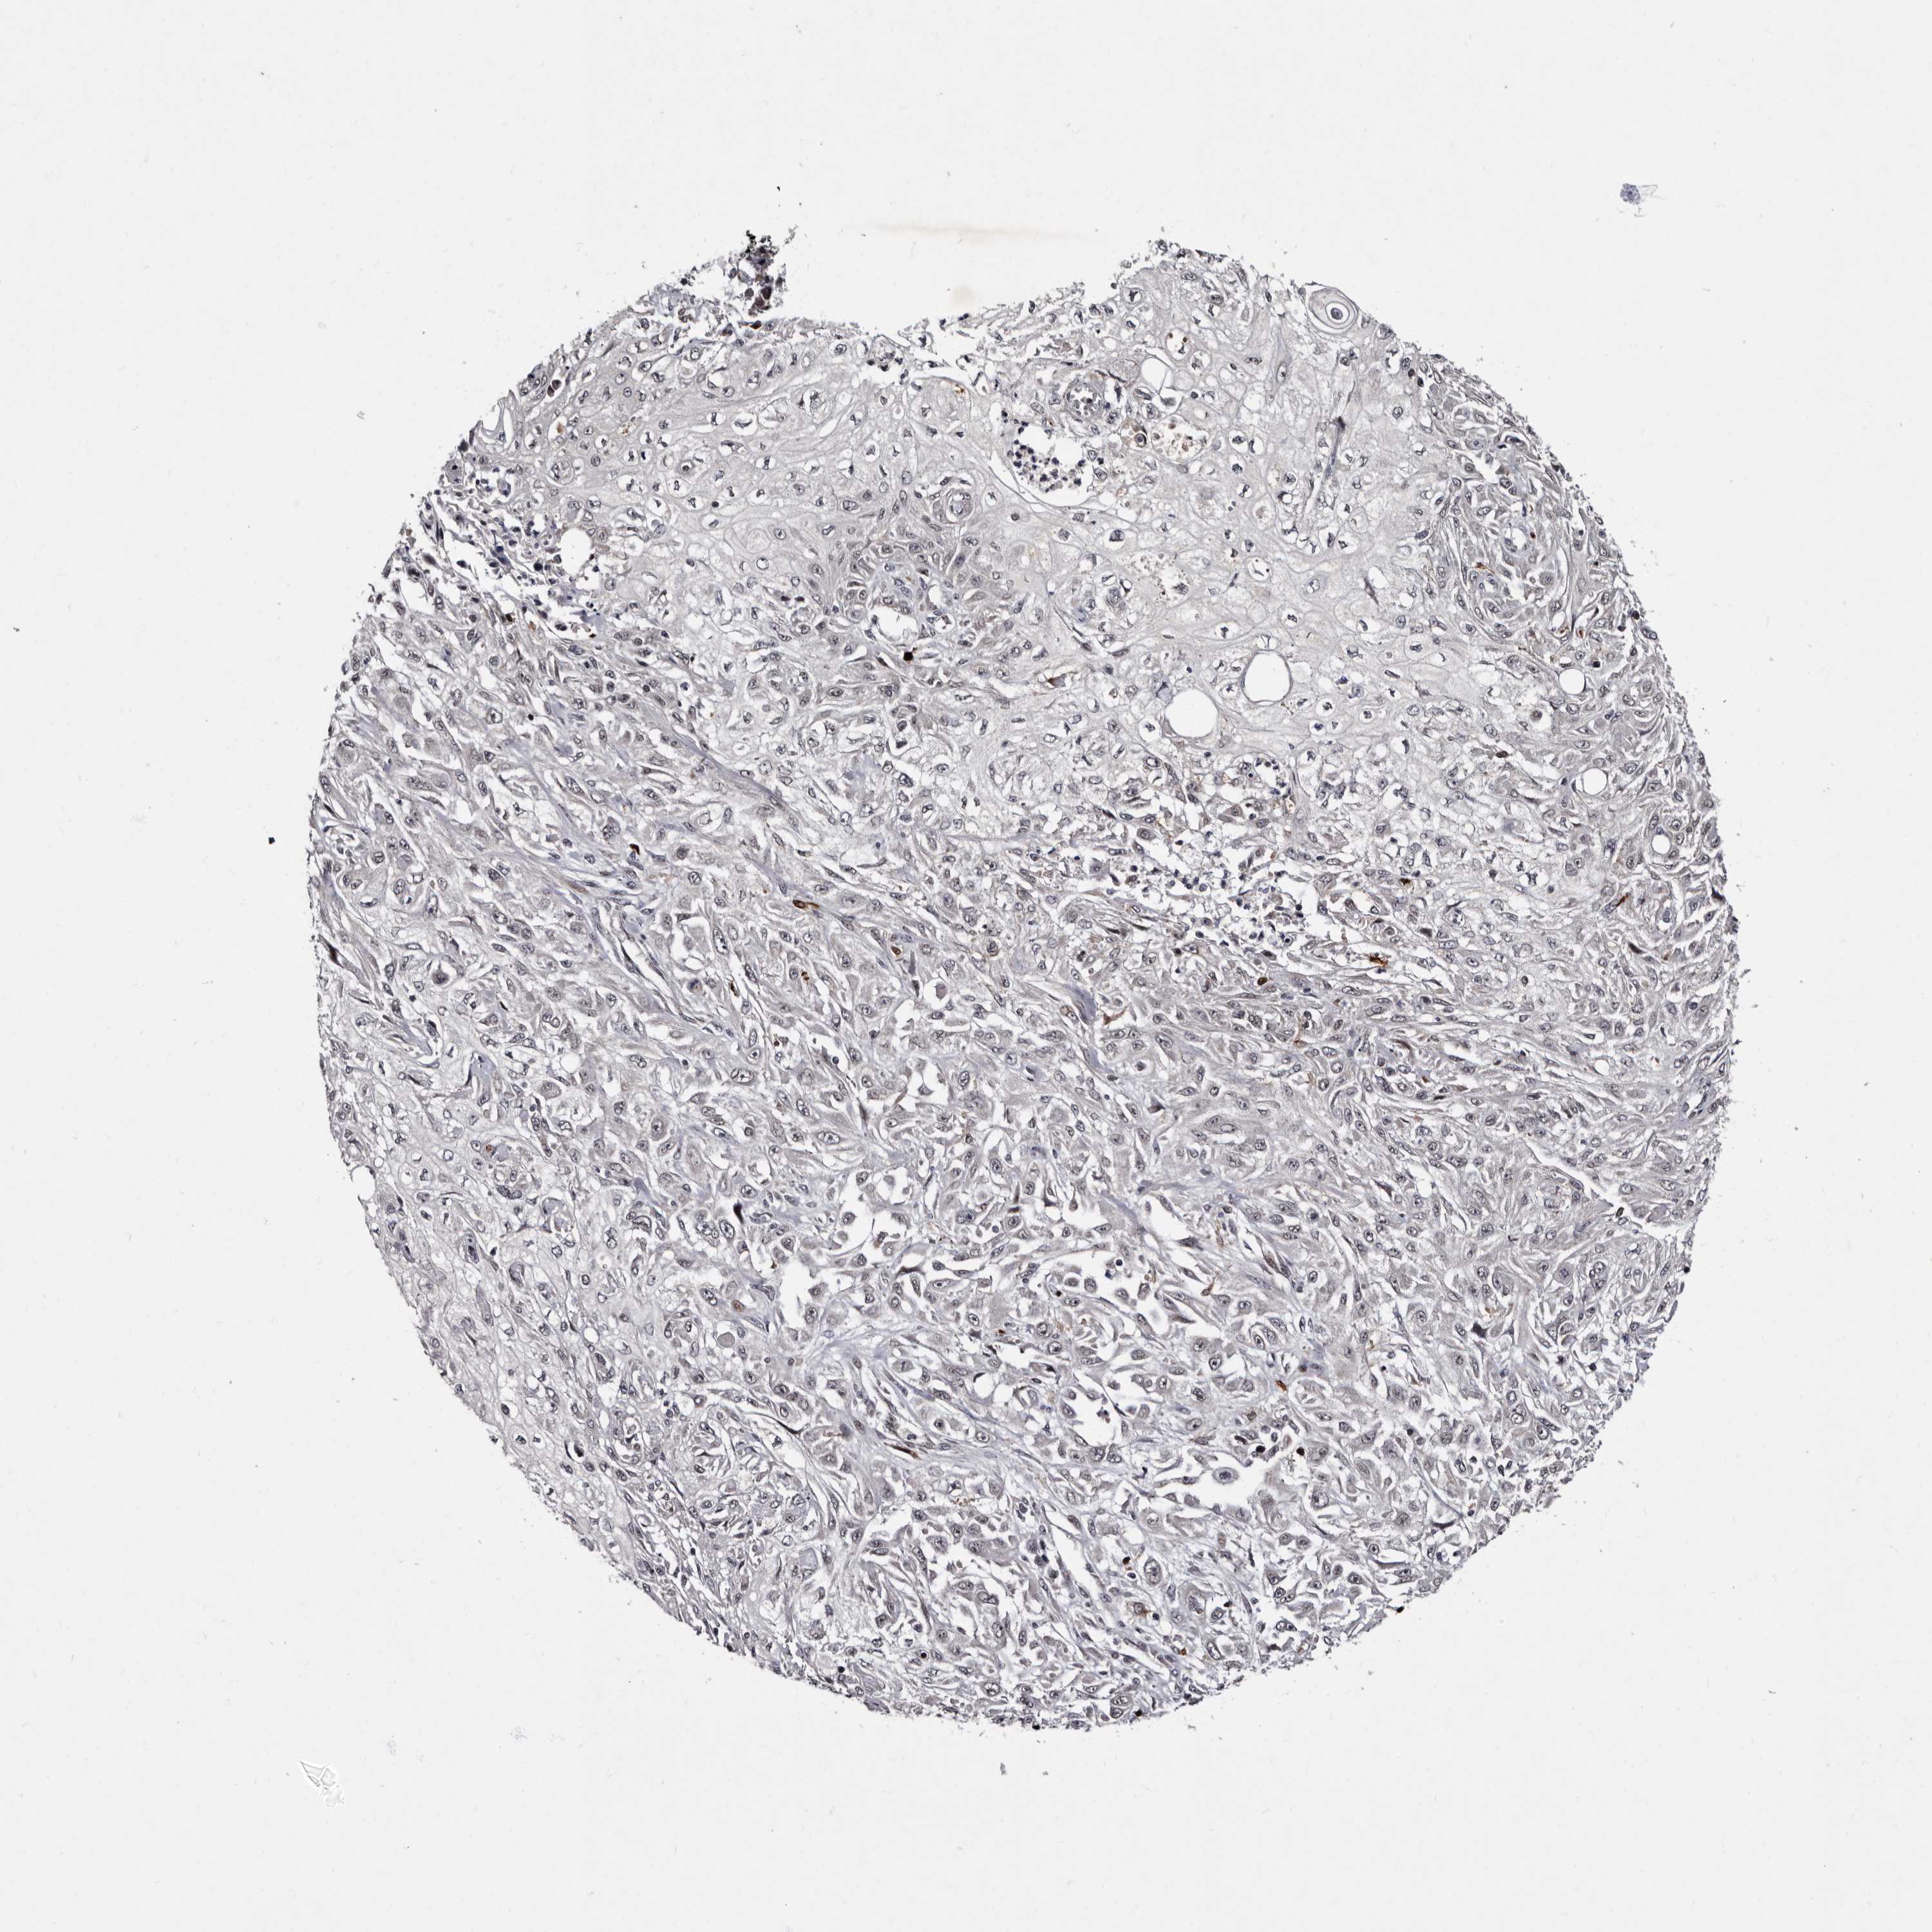

SKIN CANCER - Protein expressioni

A mouse-over function shows sample information and annotation data. Click on an image to view it in a full screen mode. Samples can be filtered based on level of antibody staining by selecting one or several of the following categories: high, medium, low and not detected. The assay and annotation is described here.

Each image is clickable and will lead to virtual microscopy that enables deeper exploration of all samples and also displays staining intensity scores, fraction scores and subcellular localization as well as patient and tissue information for each sample.

Antibody HPA025690

Staining

Not detected

Intensity

Negative

Quantity

None

Location

Squamous cell carcinoma, metastatic, NOS